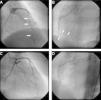

Transthoracic echocardiography revealed a small pericardial effusion with no other abnormalities. A diagnosis of myopericarditis was assumed and anti-inflammatory therapy with ibuprofen was initiated. However, the patient's recurrent chest pain persisted, associated with dynamic ECG abnormalities (transient ST-segment elevation in inferior leads) (Figure 1B) and new wall motion abnormalities on echocardiography (inferior wall hypokinesia). Given the unfavorable clinical evolution associated with a significant rise in plasma troponin I concentration and new ECG and echocardiographic abnormalities, despite anti-inflammatory therapy, cardiac catheterization was performed on the fourth day after admission. Coronary arteriography demonstrated irregularity of the larger arteries with long diffuse stenotic lesions in the left anterior descending and right coronary arteries (Figure 2A and B, arrowed), consistent with diffuse vasculitis. A myocardial biopsy showed eosinophilic myocarditis (Figure 3A) and a concomitant nasal biopsy revealed eosinophilic necrotizing granulomatous vasculitis. Immunologic study, including ANCA antibodies, was negative, while electromyography revealed left saphenous nerve mononeuropathy.

Coronary angiography at presentation showing diffuse vessel wall irregularities in the left anterior descending artery (A) and right coronary artery (B). Coronary angiography after one year of immunosuppressive therapy showing resolution of vasculopathy in the anterior descending artery (C) and right coronary artery (D).

Churg–Strauss syndrome was then diagnosed as four out of six criteria were present in this patient: (1) asthma; (2) eosinophilia; (3) mononeuropathy; (4) extravascular eosinophils.7 Pulse intravenous (i.v.) corticosteroid treatment (methylprednisolone 1 g i.v. daily for three days) was started, just after the biopsy results, followed by oral glucocorticoid therapy (prednisone 1.5 mg/kg daily) associated with cyclophosphamide (0.6 g/m2 intravenously once a month). On day one of treatment, the patient's symptoms improved significantly and levels of blood eosinophils fell to 0.02×109/l. Echocardiography performed after 18 days of treatment showed resolution of the pericardial effusion as well as of the left ventricular wall motion abnormalities. Control coronary angiography one year after initiation of therapy showed complete regression of coronary stenotic lesions (Figure 2C and D) and a myocardial biopsy confirmed resolution of eosinophilic myocarditis (Figure 3B). The patient was stable and symptom-free at one year of follow-up under chronic therapy.